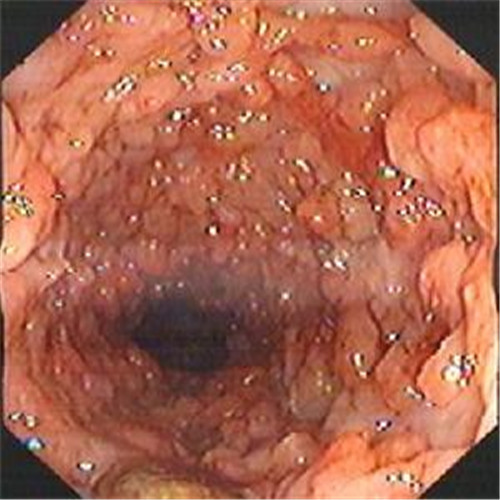

潰瘍性結腸炎圖片

潰瘍性結腸炎重度糜爛